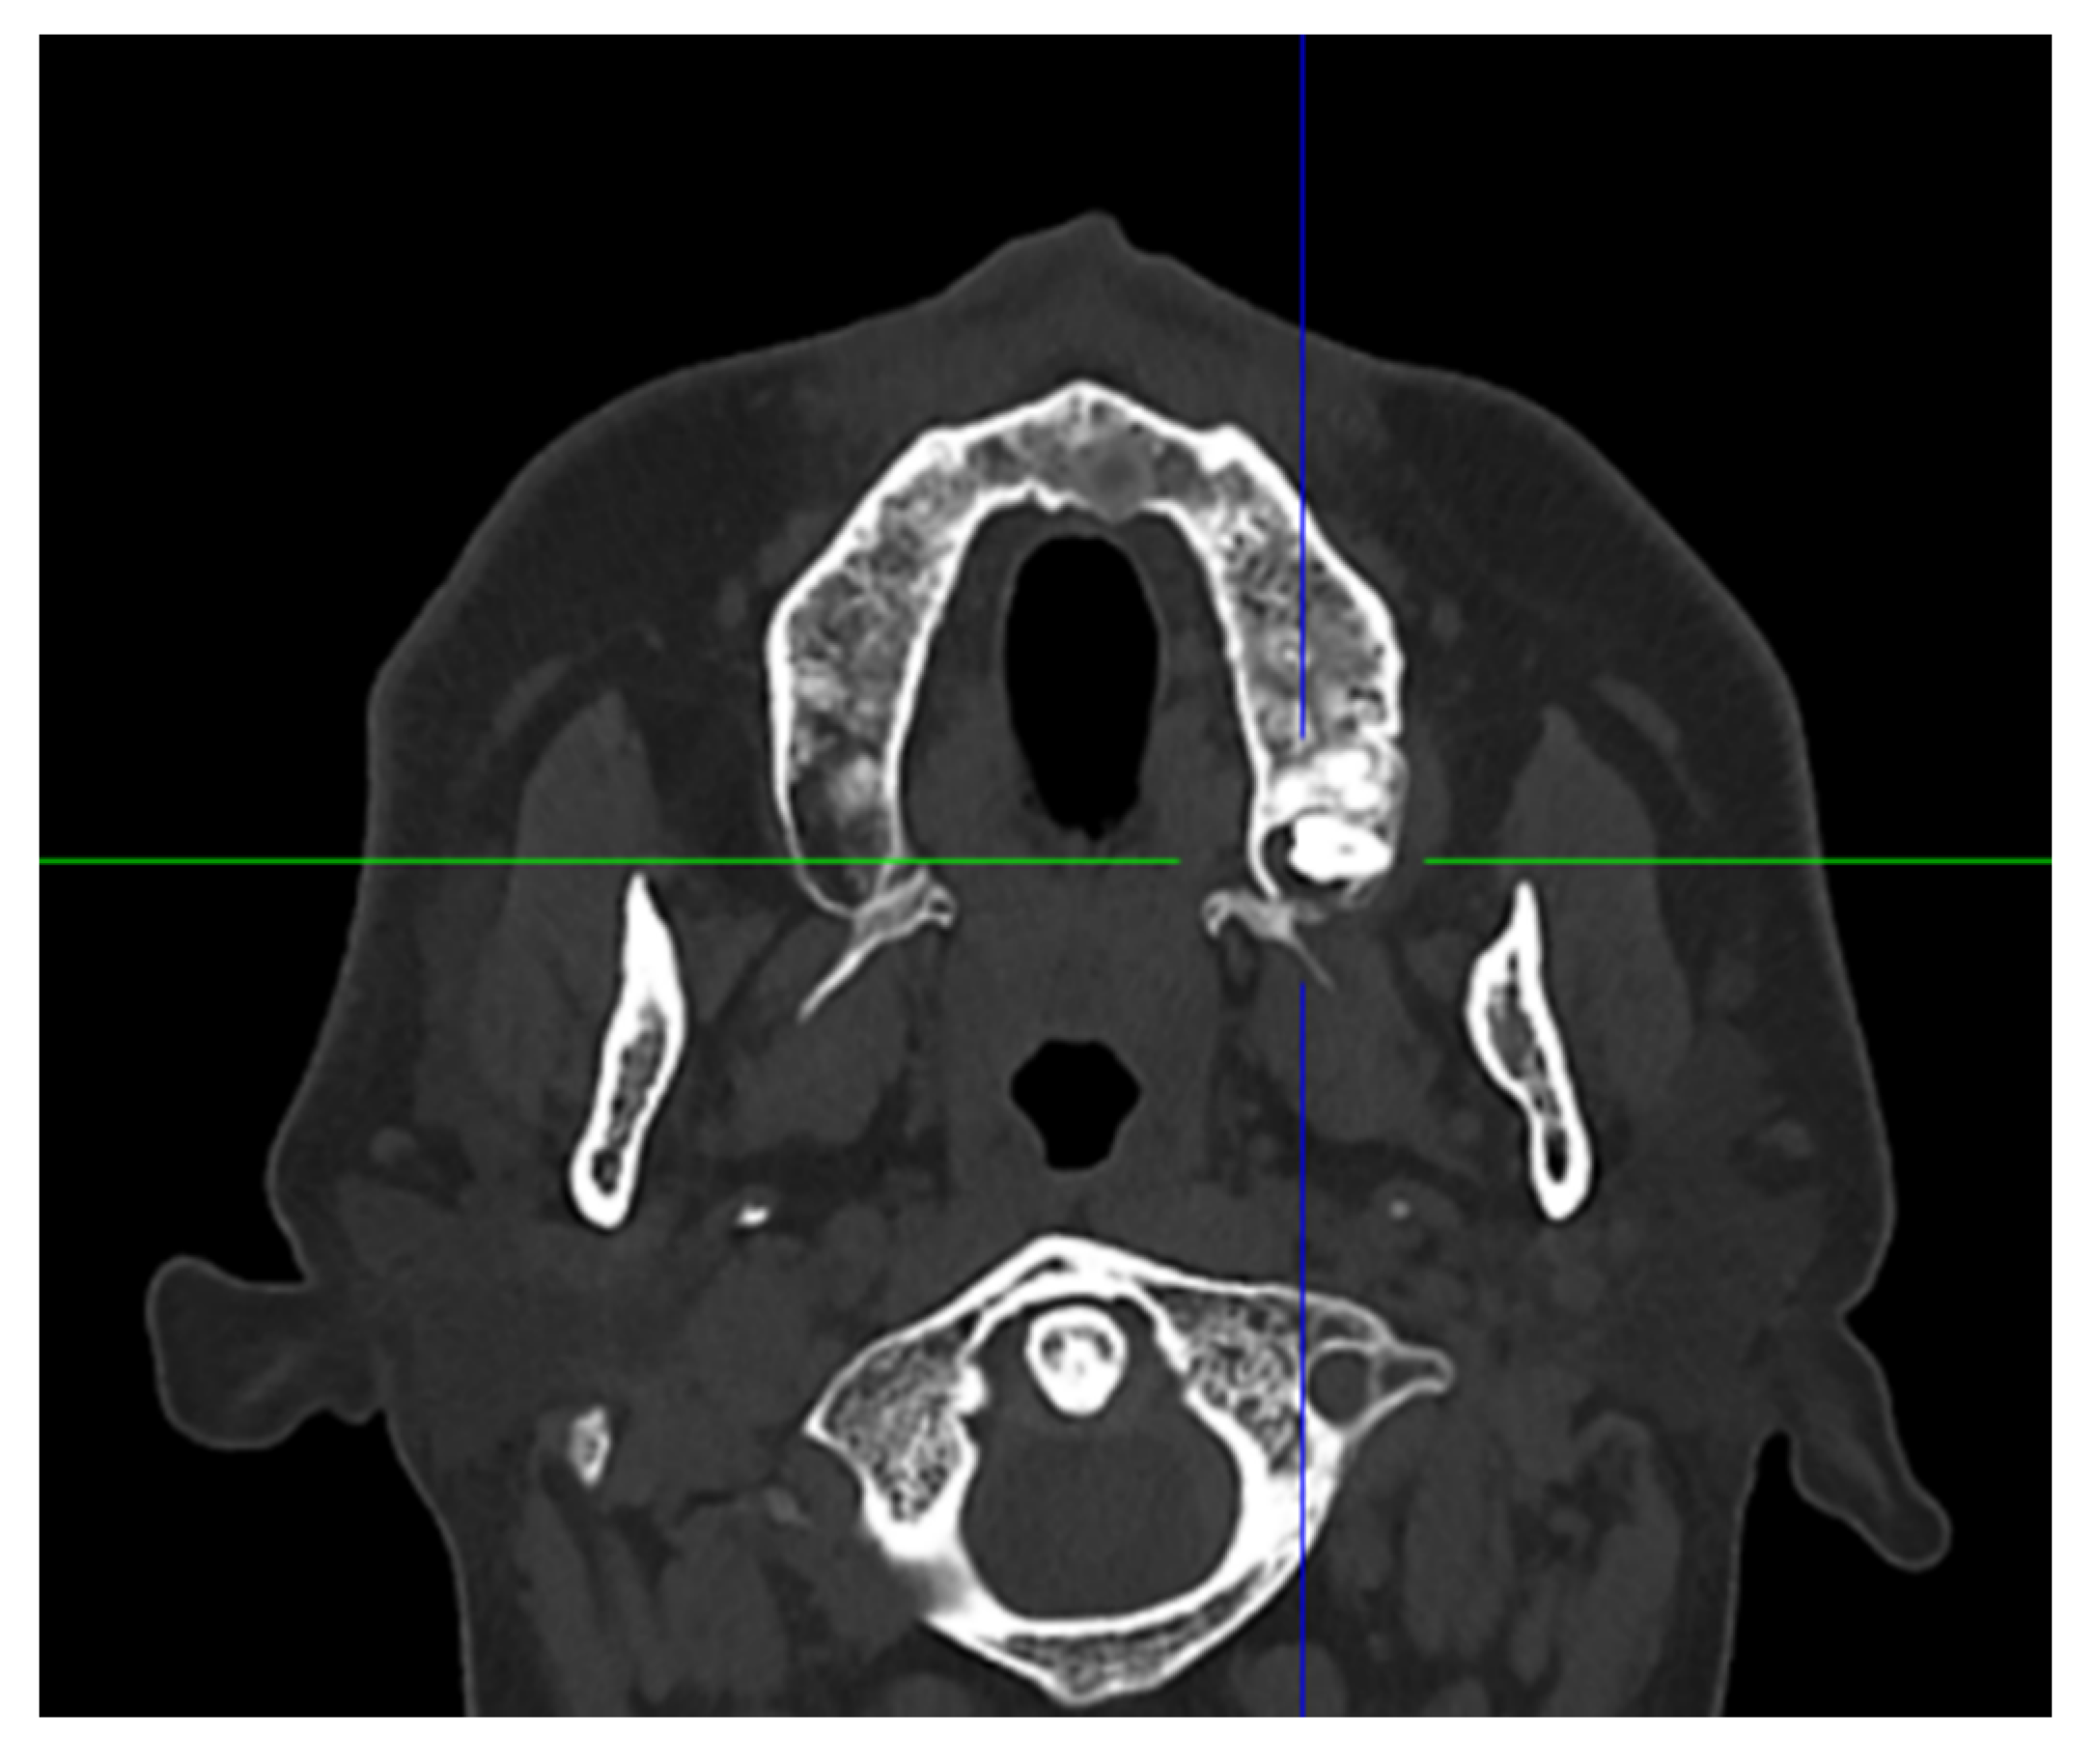

2. Case Presentation

| Present Case | M | 46 | Pain | Maxillary distomolar | Enucleation |